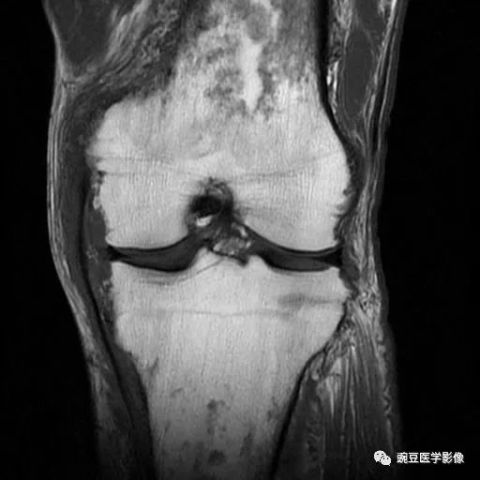

浮髌试验阳性,左膝关节MR示大量异常改变

480x480 - 12KB - JPEG